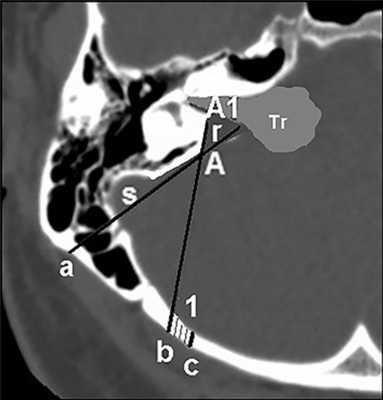

Измеряли расстояние от средней точки заднего края внутреннего слухового прохода до границ лабиринта, прибавляя расстояние безопасности 1 мм. На аксиальной компьютерной томограмме в костном окне на уровне середины внутреннего слухового прохода (рис. 3) отмеряли полученное расстояние от его края на задней стенке ВСК и отмечали точку «А1». Такое же расстояние отмеряли на задней грани пирамиды височной кости и отмечали точку «А». Соединив точки А и А1, определяли ось бурения «1».

Рис. 3. Определение точки (b) выхода оси бурения (1) на поверхность затылочной кости и зоны (r) резекции задней стенки внутреннего слухового канала. А — точка входа бурения; 1 — ось бурения; s — сигмовидный синус; а — угол хода ВСК от плоскости задней грани пирамиды височной кости.